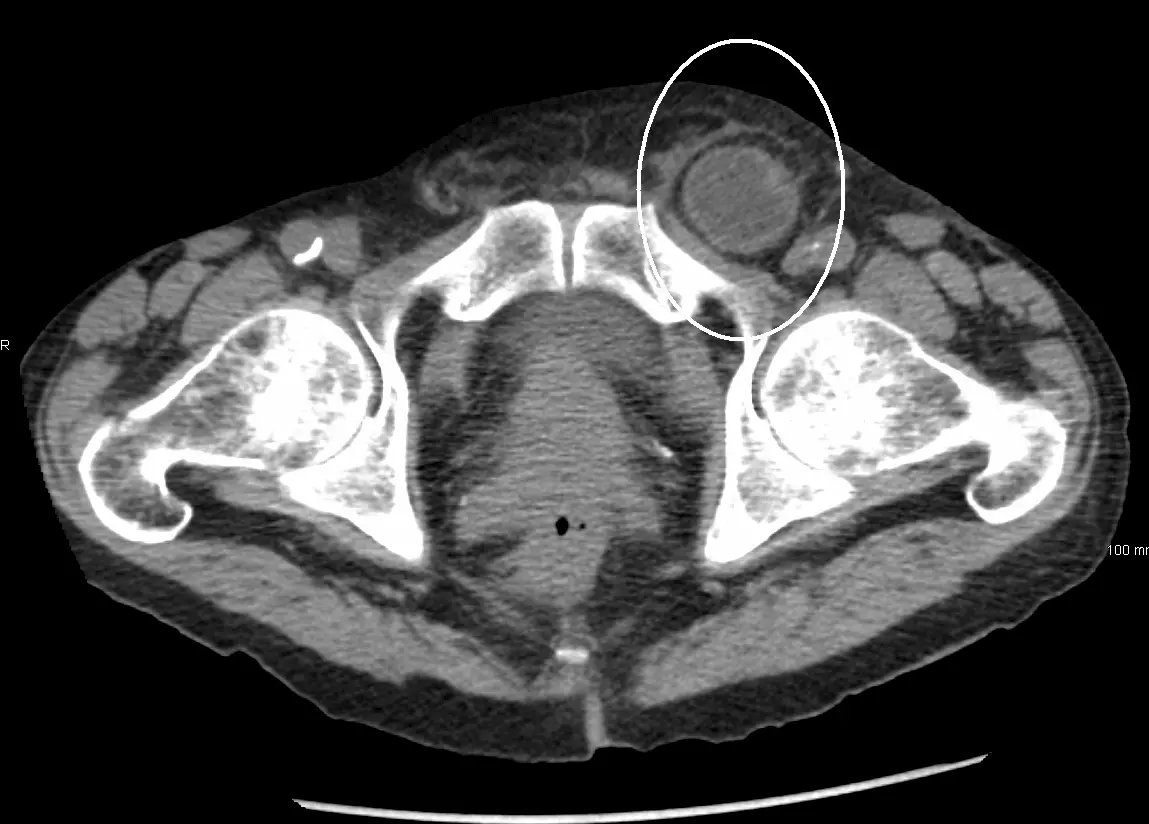

Image - A CT scan of an incarcerated inguinal hernia

- Comprise 75% of all abdominal hernias.

- More common in men than women and can descend into the scrotum.

- Most commonly occur via the indirect route (lateral to the epigastric vessels) - pass through the deep ring of the inguinal canal, follow the path of the inguinal canal and exit via the superficial ring of the inguinal canal.

- Less commonly occur via the direct route (medial to the epigastric vessels) - push through Hesselbach’s triangle (bordered by rectus abdominus, the inguinal ligament and the inferior epigastric vessels).